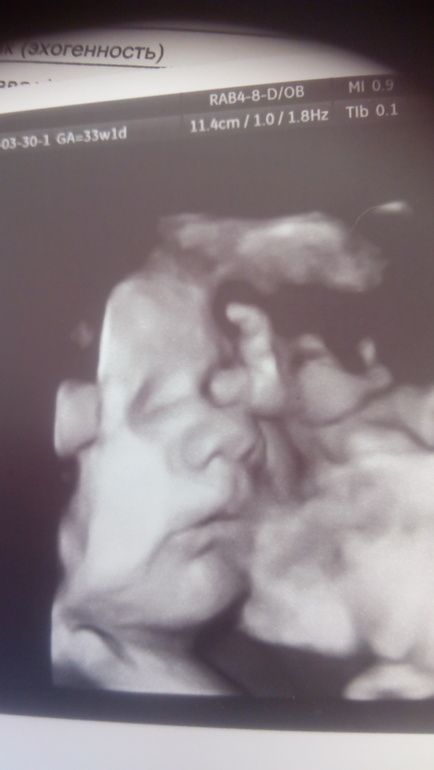

В 34 недели были на УЗИ, все отлично, растёт парень, вес уже 2350,фоткаться не желал, еле хоть такое фото словили